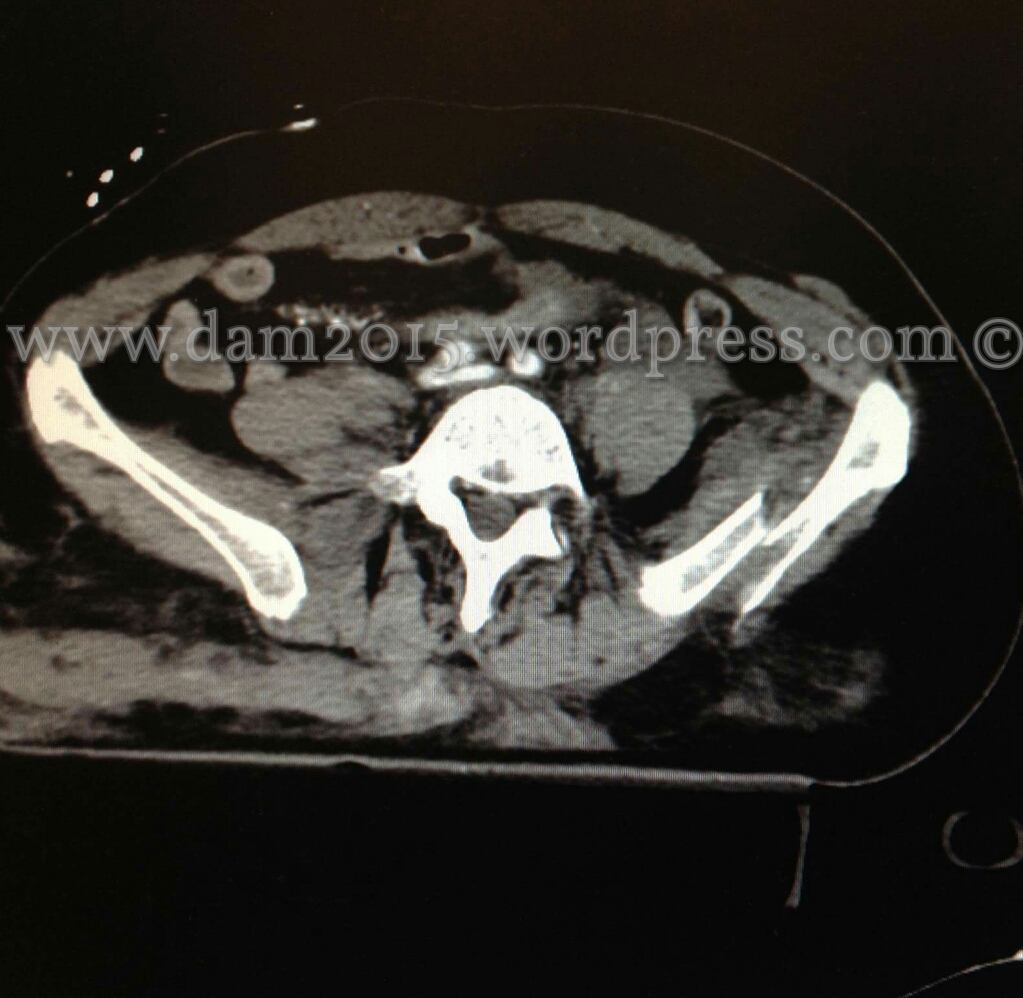

Pz donna, 56 anni.

Incidente stradale.

Shock emorragico in fratture multiple del bacino. Emoperitoneo.